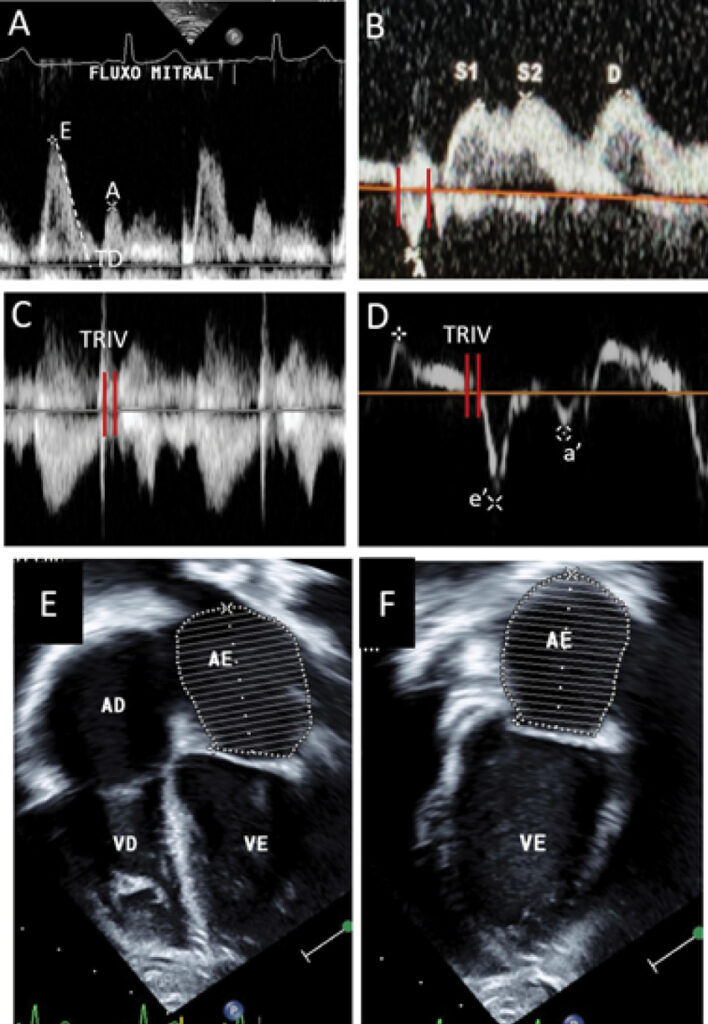

My Approach to Managing Left Ventricular Diastolic Function of Children and in Congenital Heart Disease

Echocardiography is the primary diagnostic method for assessing ventricular function in children and patients with congenital heart disease; however, it traditionally focuses on systolic function. Despite the growing interest in echocardiographic parameters for assessing diastolic function in children, diastolic dysfunction has been less investigated and, therefore, is less understood.